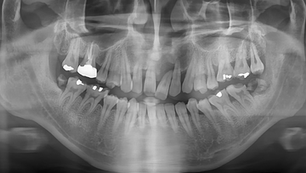

Sinus graft with lateral approach and implants placement with C-reamer in Sinus All Kit

Situation Panoramic X-ray: Due to the limited amount of remaining bone, lateral approach for the posterior part of sinus is preferred....